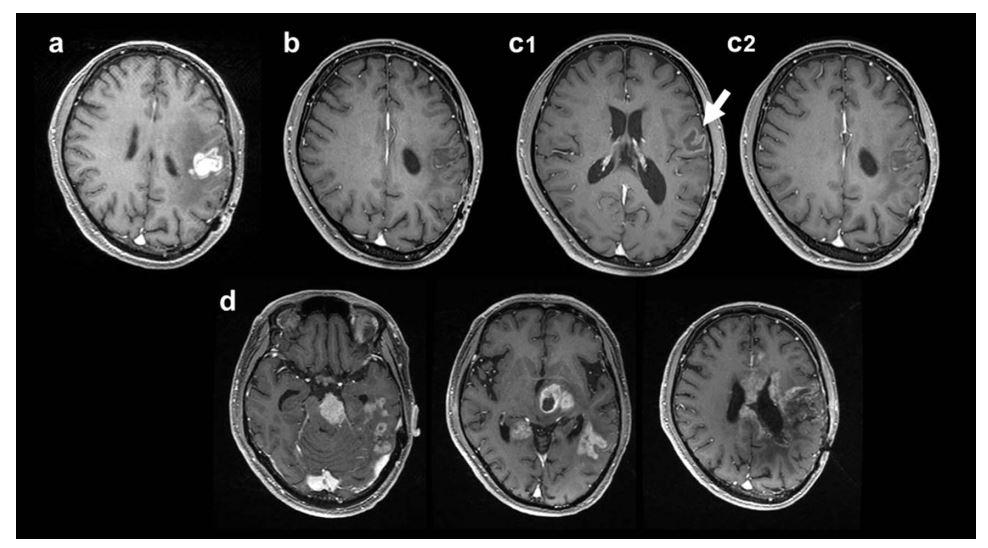

图 3 : 典型病例( 44 岁男性患者, (a) 原发 GBM 术后 8.8 个月首次复发。( b )经 BNCT 联合贝伐珠单抗治疗后 3 月肿瘤完全缓解;( 3 ) 8.2 月后照射野外肿瘤复发;( d )肿瘤进展后继续接受治疗,在 BNCT 治疗 后 36.7 月时死亡